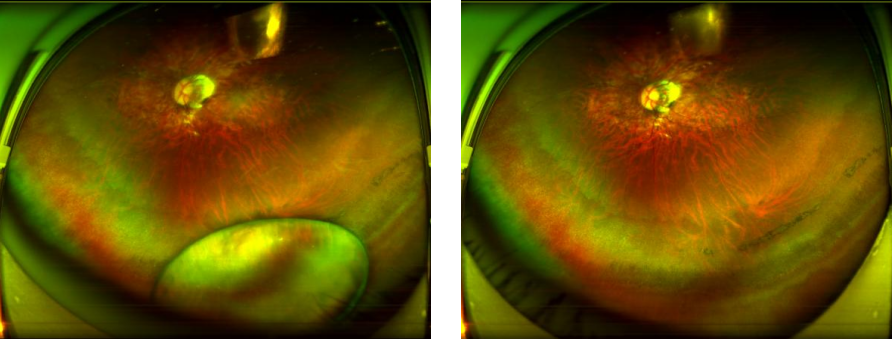

无独有偶,陆丰的欧叔在一次砍柴时,被飞溅的树枝击中右眼。眨眼间,右眼红肿起来,视力也急剧下降。在亲友的推荐下,欧叔得知深圳华厦眼科医院院长赵铁英教授在复杂眼外伤治疗领域临床经验丰富,便满怀希望地来到了赵铁英教授的门诊。

图:欧叔术前(左)术后(右)眼底广角照相图

图:欧叔术前(左)术后(右)眼前段照相

此时,他的右眼前房积脓,晶体后囊、玻璃体混浊,仅能模糊看到距离眼前30厘米的指数。赵铁英院长根据病史临床表现及辅助检查,迅速为欧叔制定了先药物抗感染密切观察,前房积脓明显消退吸收后,由朱远飞主任对其巩膜伤口进行了探查清创缝合,待眼部炎症反应进一步好转,磁共振再排除眼内木质异物,赵铁英院长同朱远飞主任一起安全地进行了伤眼前后段联合手术,出院前的检查欧叔的右眼视力已经恢复到0.4了。欧叔静静地躺在病床上,看着病房的一切。他声音略带颤抖地说道:“多亏了赵院长和朱主任及深圳华厦眼科医院的全体工作人员,是她们给了我这只眼睛(右眼)重新看清事物的机会。”